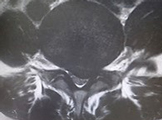

せぼねの変形や椎間板の傷み具合、不安定性の有無、脊柱管の狭さ、またせぼね全体のバランスなどを見るためにX線検査やCT検査、MRI検査などを行います。進行例では脊柱管の狭さをより詳しく評価するために入院して脊髄造影検査や、同時にどの神経が痛みの原因となっているかを明らかにするために神経の枝に直接麻酔薬を注入する選択的神経根ブロックを行う場合があります。成人期では血管性の下肢の痛みがないか評価するために両手足の血圧を測ったり、骨粗鬆症の有無を評価するために骨密度検査を行うこともあります。

椎間板の傷み具合や膨隆の程度、不安定性の有無、またせぼね全体のバランスなどを見るためにX線検査やCT検査、MRI検査などを行います。その他、入院して行う脊髄造影検査や、神経の枝に直接麻酔薬を注入する選択的神経根ブロック、あるいは椎間板造影や椎間板ブロックを行うこともあります。成人期では血管性の下肢の痛みがないか評価するために両手足の血圧を測ったり、骨粗鬆症の有無を評価するために骨密度検査を行うこともあります。

せぼねの変形や椎間板の傷み具合、すべりや不安定性の程度、脊柱管の狭さ、またせぼね全体のバランスなどを見るためにX線検査やCT検査、MRI検査などを行います。進行例では脊柱管の狭さをより詳しく評価するために入院して脊髄造影検査や、同時にどの神経が痛みの原因となっているかを明らかにするために神経の枝に直接麻酔薬を注入する選択的神経根ブロックを行う場合があります。成人期では血管性の下肢の痛みがないか評価するために両手足の血圧を測ったり、骨粗鬆症の有無を評価するために骨密度検査を行うこともあります。

せぼねの変形や椎間板の傷み具合、すべりや不安定性の有無、脊柱管の狭さ、またせぼね全体のバランスなどを見るためにX線検査やCT検査、MRI検査などを行います。進行例では脊柱管の狭さをより詳しく評価するために入院して脊髄造影検査や、同時にどの神経が痛みの原因となっているかを明らかにするために神経の枝に直接麻酔薬を注入する選択的神経根ブロックを行う場合があります。成人期では血管性の下肢の痛みがないか評価するために両手足の血圧を測ったり、骨粗鬆症の有無を評価するために骨密度検査を行うこともあります。